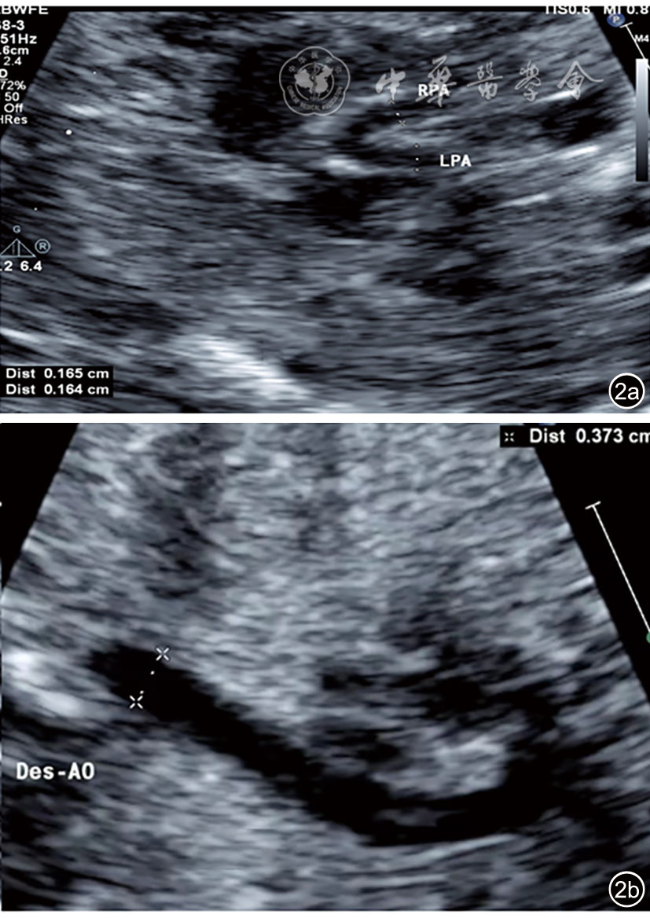

2.胎儿超声心动图检查:(1)胎儿生物学指标测量,确定孕龄;(2)测量并计算胎儿心胸比(cardiothoracic ratio,CTR);(3)收缩期测量胎儿主动脉瓣环(aorta,AO)内径及肺动脉瓣环(pulmonary,PA)内径,计算PA/AO;(4)胎儿MGI的测定:留存清晰显示LPA、RPA、膈肌水平降主动脉(descending aorta,DAO)、动脉导管(ductus arteriosus,DA)的动态图。测量LPA、RPA、DAO、DA内径,所有数值均在心室收缩期完成7图12),至少测量3次,取平均值。计算MGI公式为:(LPA内径+RPA内径)/膈肌水平DAO内径。所有图像采集均由同一名具有10年以上胎儿超声心动图经验的高年资医师完成。图像的后期测量及运算均由另一位具有3年以上胎儿超声心动图经验的医师完成。

图1 超声测量正常胎儿McGoon指数。图a为肺动脉长轴切面分别测量胎儿左肺动脉和右肺动脉内径;图b为胎儿胸腹部长轴切面测量正常胎儿膈肌水平降主动脉内径

注:RPA为右肺动脉;LPA为左肺动脉

图2 超声测量法洛四联症胎儿McGoon指数。图a为法洛四联症胎儿肺动脉长轴切面显示肺动脉主干及左肺动脉和右肺动脉明显狭窄,分别测量左肺动脉和右肺动脉内径;图b为胎儿胸腹部长轴切面测量法洛四联症胎儿膈肌水平降主动脉内径

注:RPA为右肺动脉;LPA为左肺动脉;Des-AO为降主动脉内径